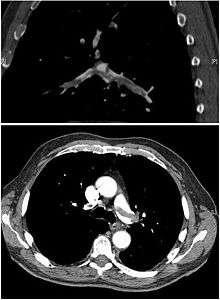

CT pulmonary angiography showing a "saddle embolus" at the bifurcation of the pulmonary artery and thrombus burden in the lobar branches of both main pulmonary arteries.

CT pulmonary angiography is the recommended first line diagnostic imaging test in most people.[43] Historically, the gold standard for diagnosis was pulmonary angiography, but this has fallen into disuse with the increased availability of non-invasive techniques. Ultrasound of the legs can confirm the presence of a PE but cannot rule it out.[44]

Non-invasive imaging

CT pulmonary angiography (CTPA) is a pulmonary angiogram obtained using computed tomography (CT) with radiocontrast rather than right heart catheterization. Its advantages are clinical equivalence, its non-invasive nature, its greater availability to people, and the possibility of identifying other lung disorders from the differential diagnosis in case there is no pulmonary embolism. Assessing the accuracy of CT pulmonary angiography is hindered by the rapid changes in the number of rows of detectors available in multidetector CT (MDCT) machines.[45] According to a cohort study, single-slice spiral CT may help diagnose detection among people with suspected pulmonary embolism.[46] In this study, the sensitivity was 69% and specificity was 84%. In this study which had a prevalence of detection was 32%, the positive predictive value of 67.0% and negative predictive value of 85.2% (click here to adjust these results for people at higher or lower risk of detection). However, this study's results may be biased due to possible incorporation bias, since the CT scan was the final diagnostic tool in people with pulmonary embolism. The authors noted that a negative single slice CT scan is insufficient to rule out pulmonary embolism on its own. A separate study with a mixture of 4 slice and 16 slice scanners reported a sensitivity of 83% and a specificity of 96%, which means that it is a good test for ruling out a pulmonary embolism if it is not seen on imaging and that it is very good at confirming a pulmonary embolism is present if it is seen. This study noted that additional testing is necessary when the clinical probability is inconsistent with the imaging results.[47] CTPA is non-inferior to VQ scanning, and identifies more emboli (without necessarily improving the outcome) compared to VQ scanning.[48]